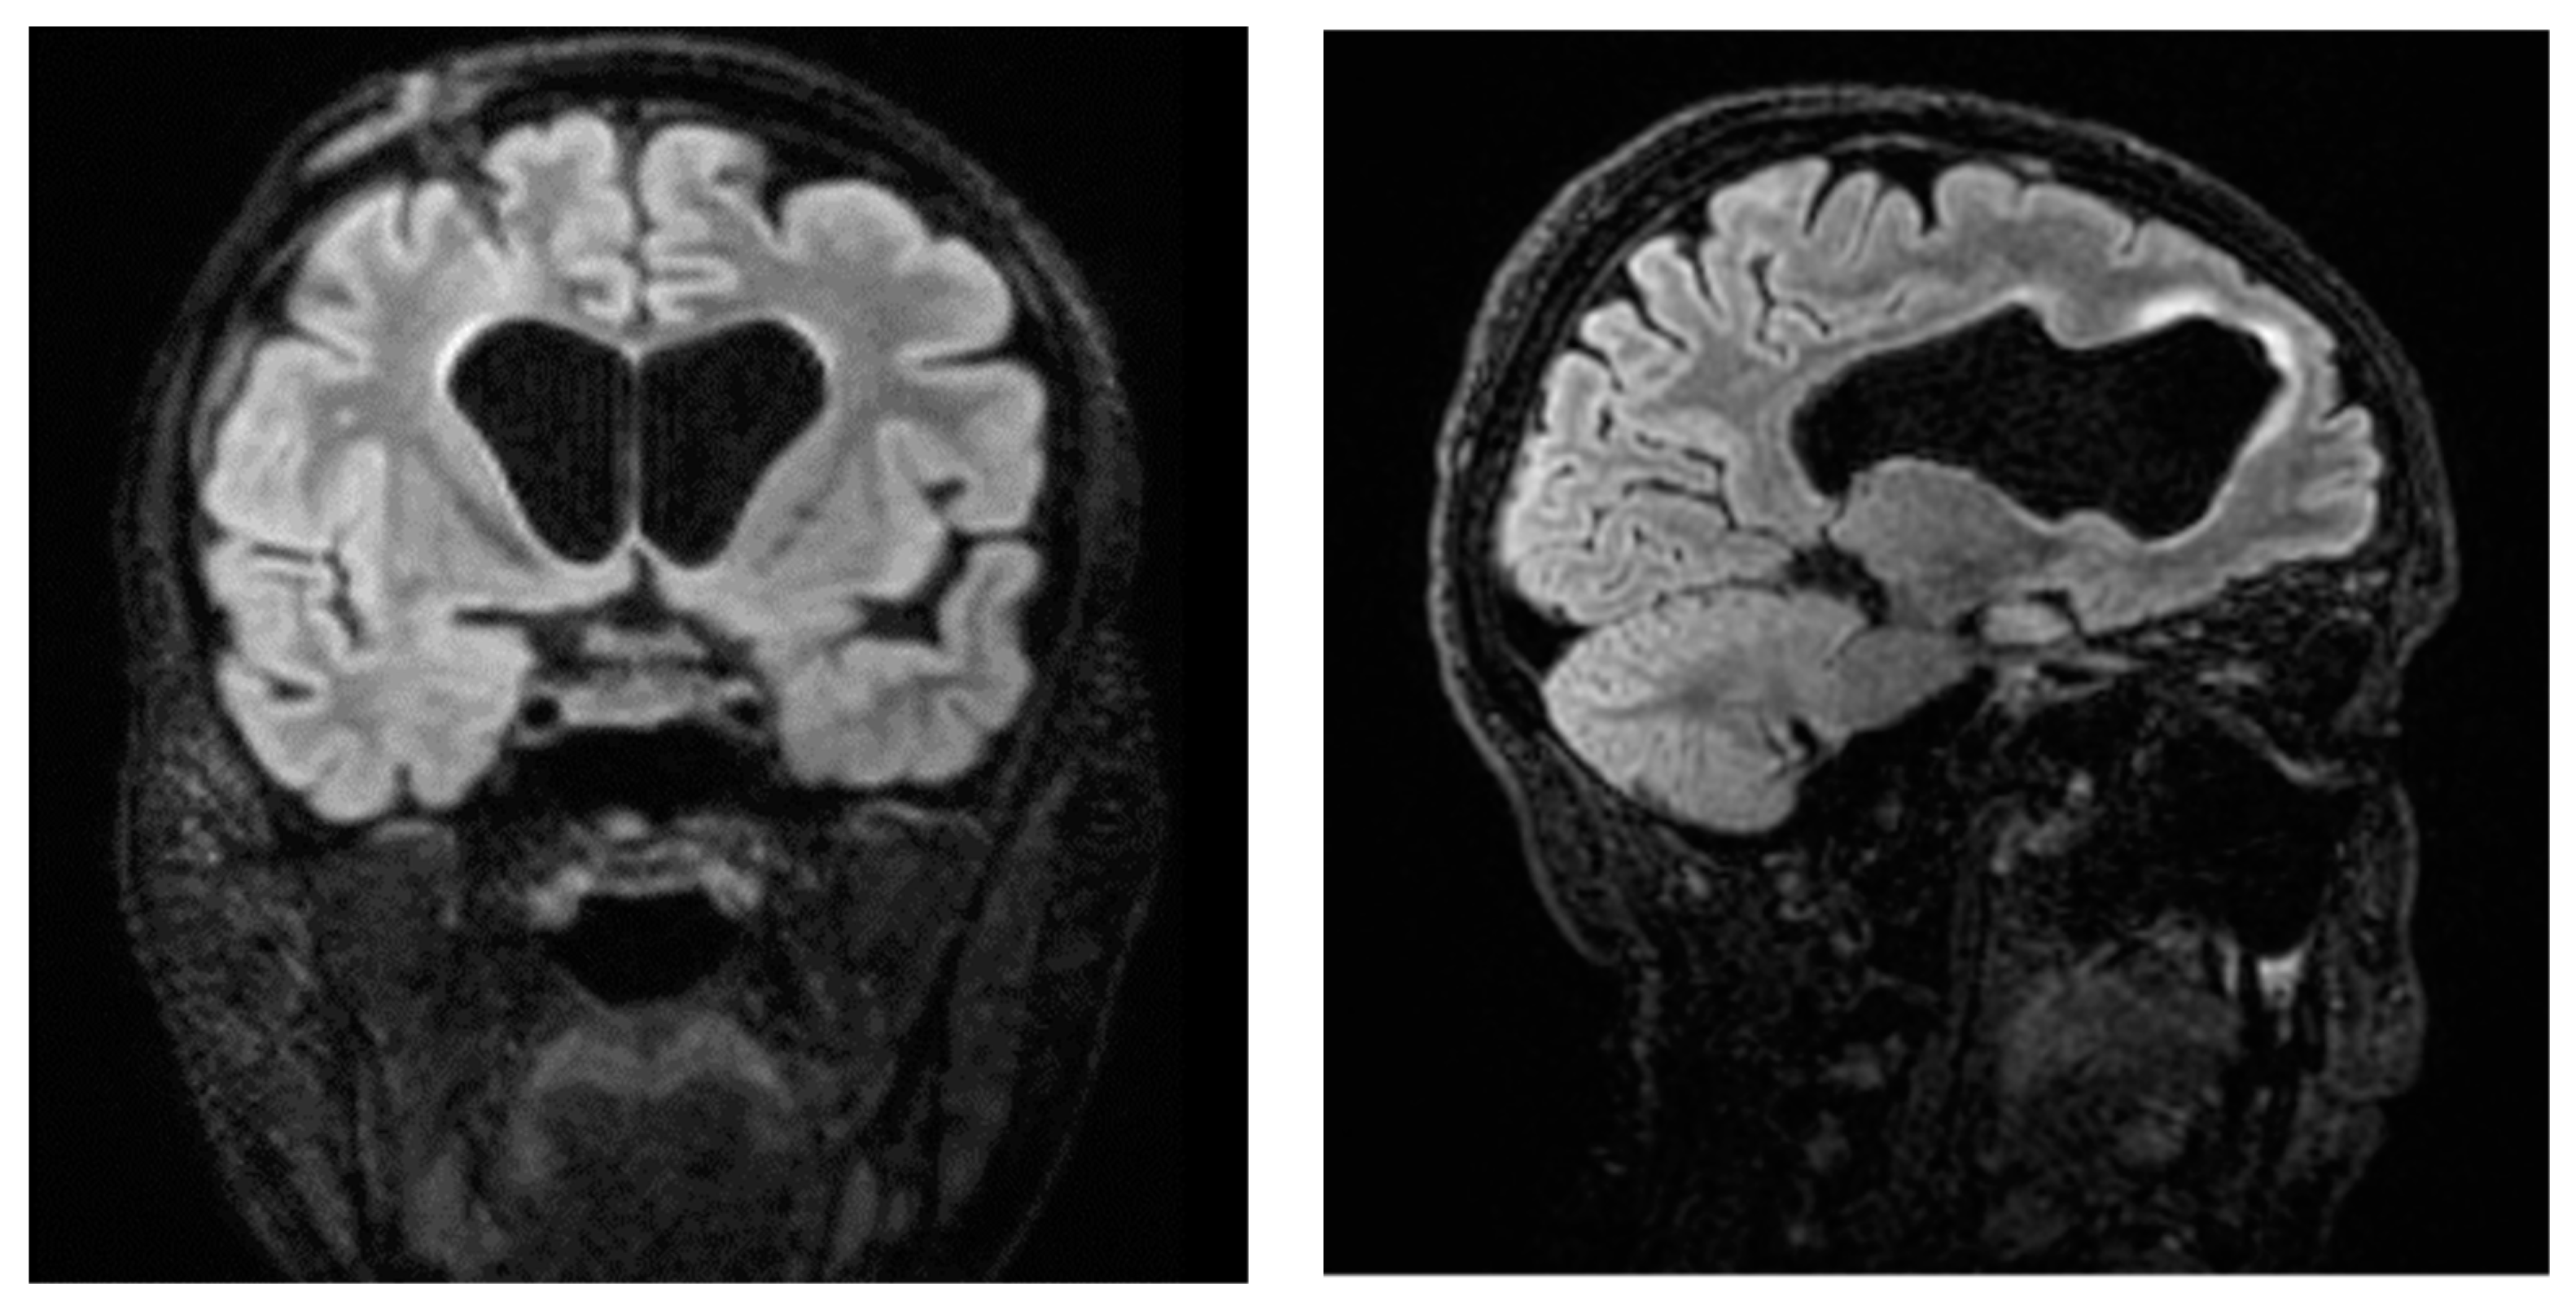

A Difficult Case of Ventriculitis in a 40-Year-Old Woman with Acute Myeloid Leukemia

2. Case Report